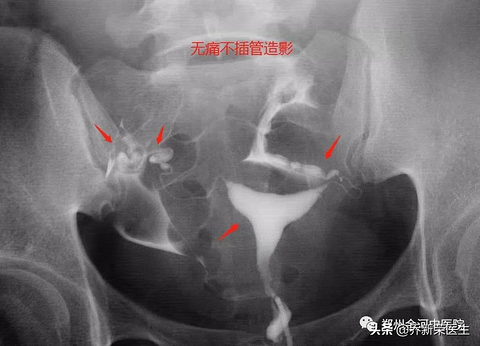

输卵管造影检查可以无痛吗?做造影有哪些注意事项?

乔新荣医生 一年以上不怀孕的女性朋友,子宫输卵管造影检查(特指X线下)是必查项目,但是没有做过的女性朋友都会有很多疑问也有很多担心,今天就常见问题一一解答。 一、听说输卵管造影很痛,天生怕痛怎么办? 一般的气囊插管式确实存在一定痛苦,有不少女性因为操作带来的疼痛产生晕厥、强烈不适,甚至有些人为了躲避这种检查,选择直接手术或者直接试管。 其实目前临床有一种不插管式、无痛造影,过程简单,就像取白带一样